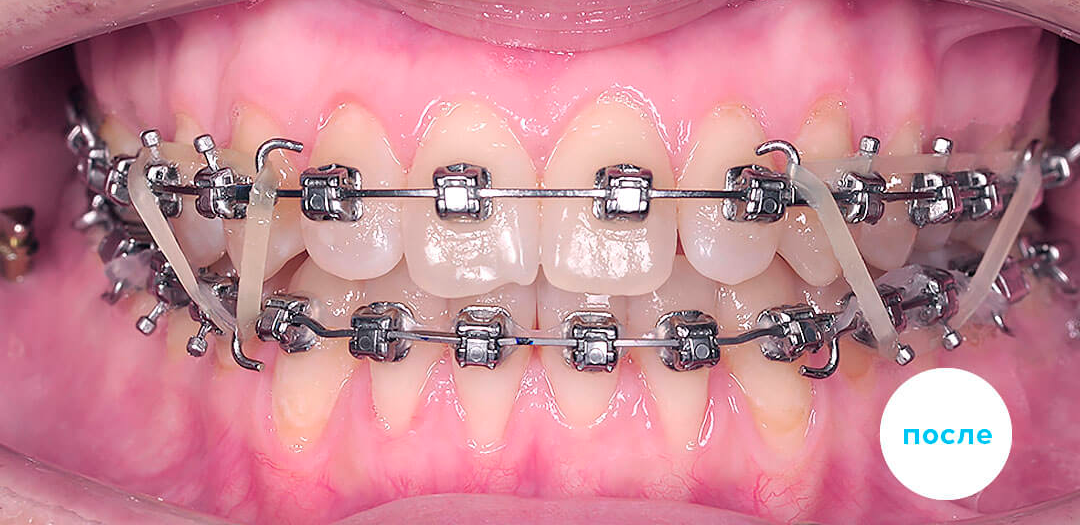

Ортодонтическое лечение взрослых проводится с использованием следующих методик:

Результаты лечения